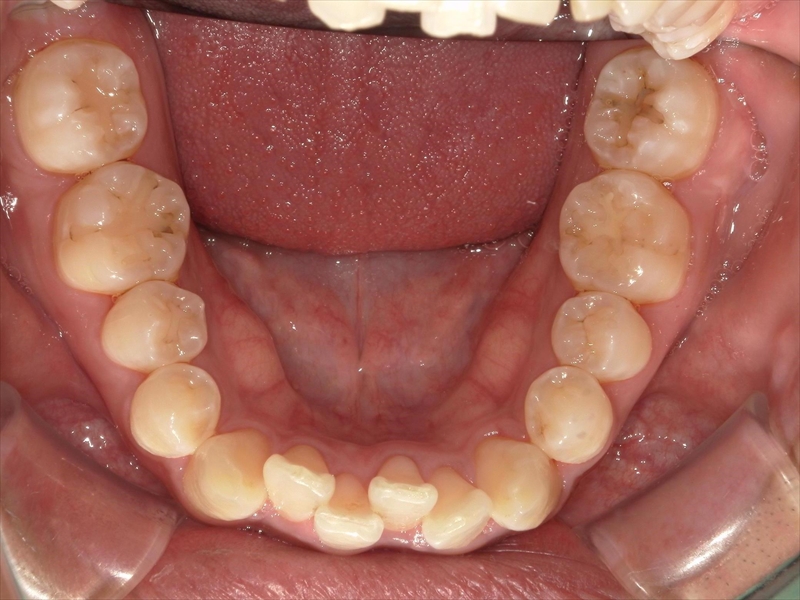

- 上あごの前歯がV字状の出っ歯

- 下あごの前歯もがたついている(叢生)

- 上あごに対して下あごがかなり小さい(過蓋咬合)

前歯のねじれ(V字)と出っ歯を下げるスペースを確保のため、両側1~5番目を0.2~0.5ミリ(計4ミリ)削ることと、奥歯から順に奥へ下げながら外側へ広げる計画を立案しました。

上あご同様、スペース確保のため、両側1~5番目までを各0.5ミリ(計5.5ミリ)削ることと、奥歯から順に奥へ下げながら外側へ広げる計画を立案しました。